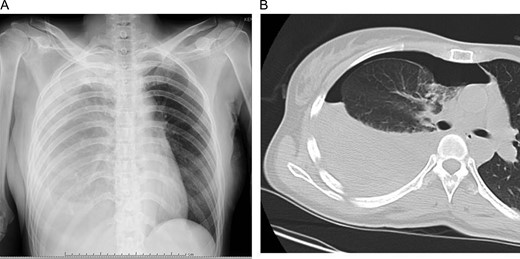

A 45-year-old woman was referred to our hospital with sudden chest pain. She came on foot and demonstrated normal consciousness. Her blood pressure on admission was 120/80 mmHg, heart rate 80/min and SpO2 on room air 98%. Her hemoglobin level on a blood test was 11.4 mg/dl. Chest X-ray and computed tomography (CT) revealed right pneumothorax with 30% of lung collapse and niveau level (Fig. 1A and B). We inserted a 24-Fr thoracic drain. After 800 ml of blood and air was evacuated immediately, the outflow of the blood from the drainage tube stopped. Because her vital signs were stable and there was no outflow of blood from the drainage tube, we continued conservative therapy with chest drainage and fluid infusion.

Initial chest X-ray (A) and computed tomography (B) revealed right pneumothorax with 30% lung collapse and niveau level.